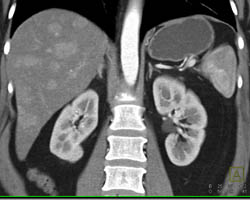

Hemangioma